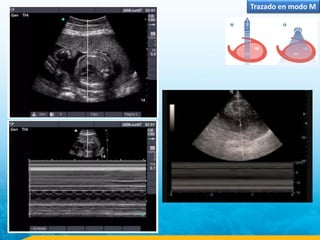

Trazado en modo M

Cuantificación de los espesores y diámetros ventriculares

izquierdos en un eco normal. SIV: septo interventricular; PP:

pared posterior; DTD: diámetro telediastólico; DTS: diámetro

telesistólico.